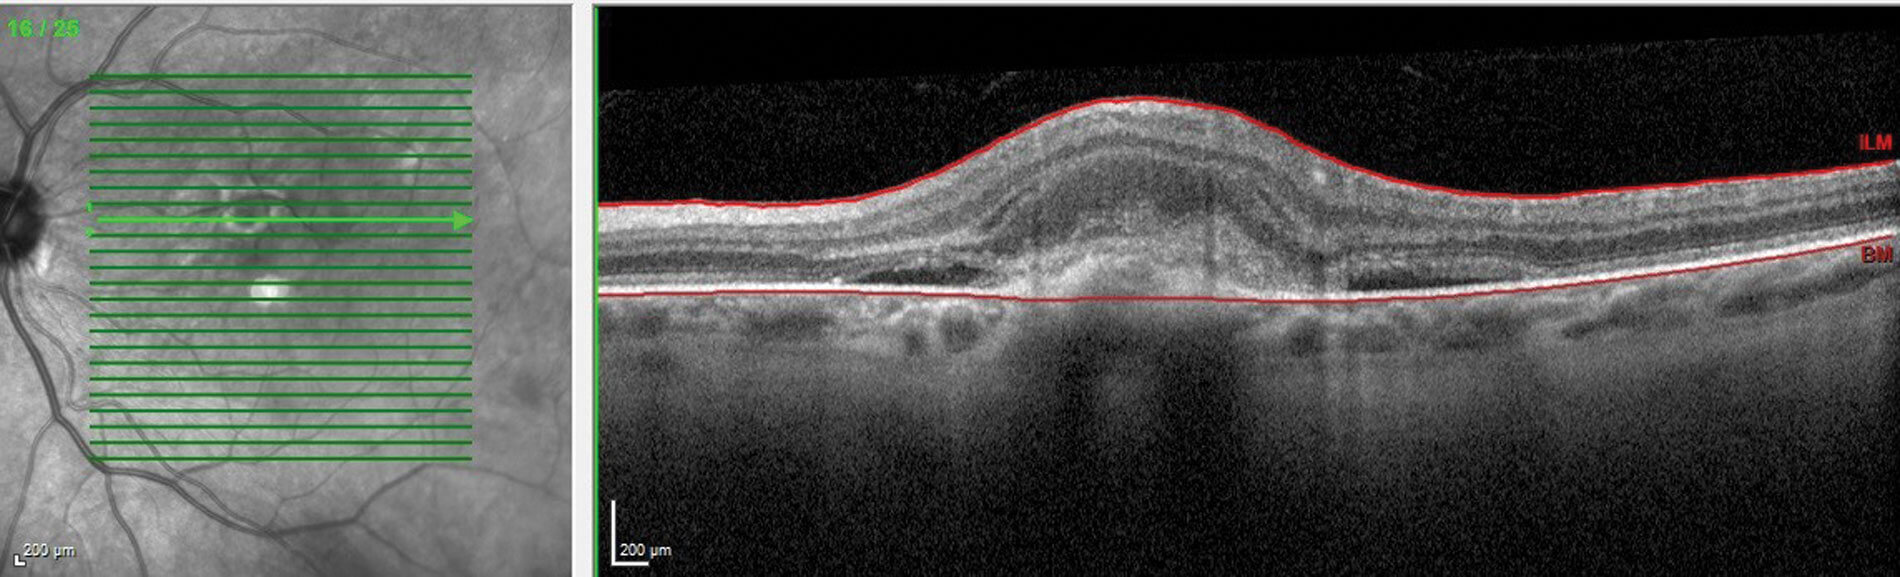

Figure 4: OCT macula showing a myopic CNV.

Figure 5: OCT macula of the same patient after receiving the first dose of anti-VEGF.

In myopia, the neovascular membrane predominantly is of type II [3]. In optical coherence tomography (OCT), the neovascular membrane appears as a hyperreflective lesion in the subretinal region (Figure 4). The most preferred treatment option for myopic CNV is anti-VEGF (Figure 5 shows the organised hyperreflective material after anti-VEGF treatment). Fundus fluorescein angiography is considered the gold-standard in investigating and assessing the activity of CNV [14]. Recently, OCT angiography (OCT-A) serves as a useful non-invasive tool to diagnose neovascularisation. In OCT-A, the neovascular membrane can appear as a lazy wheel-shaped lesion, tiny capillary branching, or as an anastomotic loop [14].